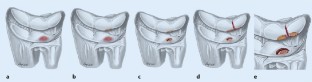

Fig. 5

Fig. 6

Fig. 7